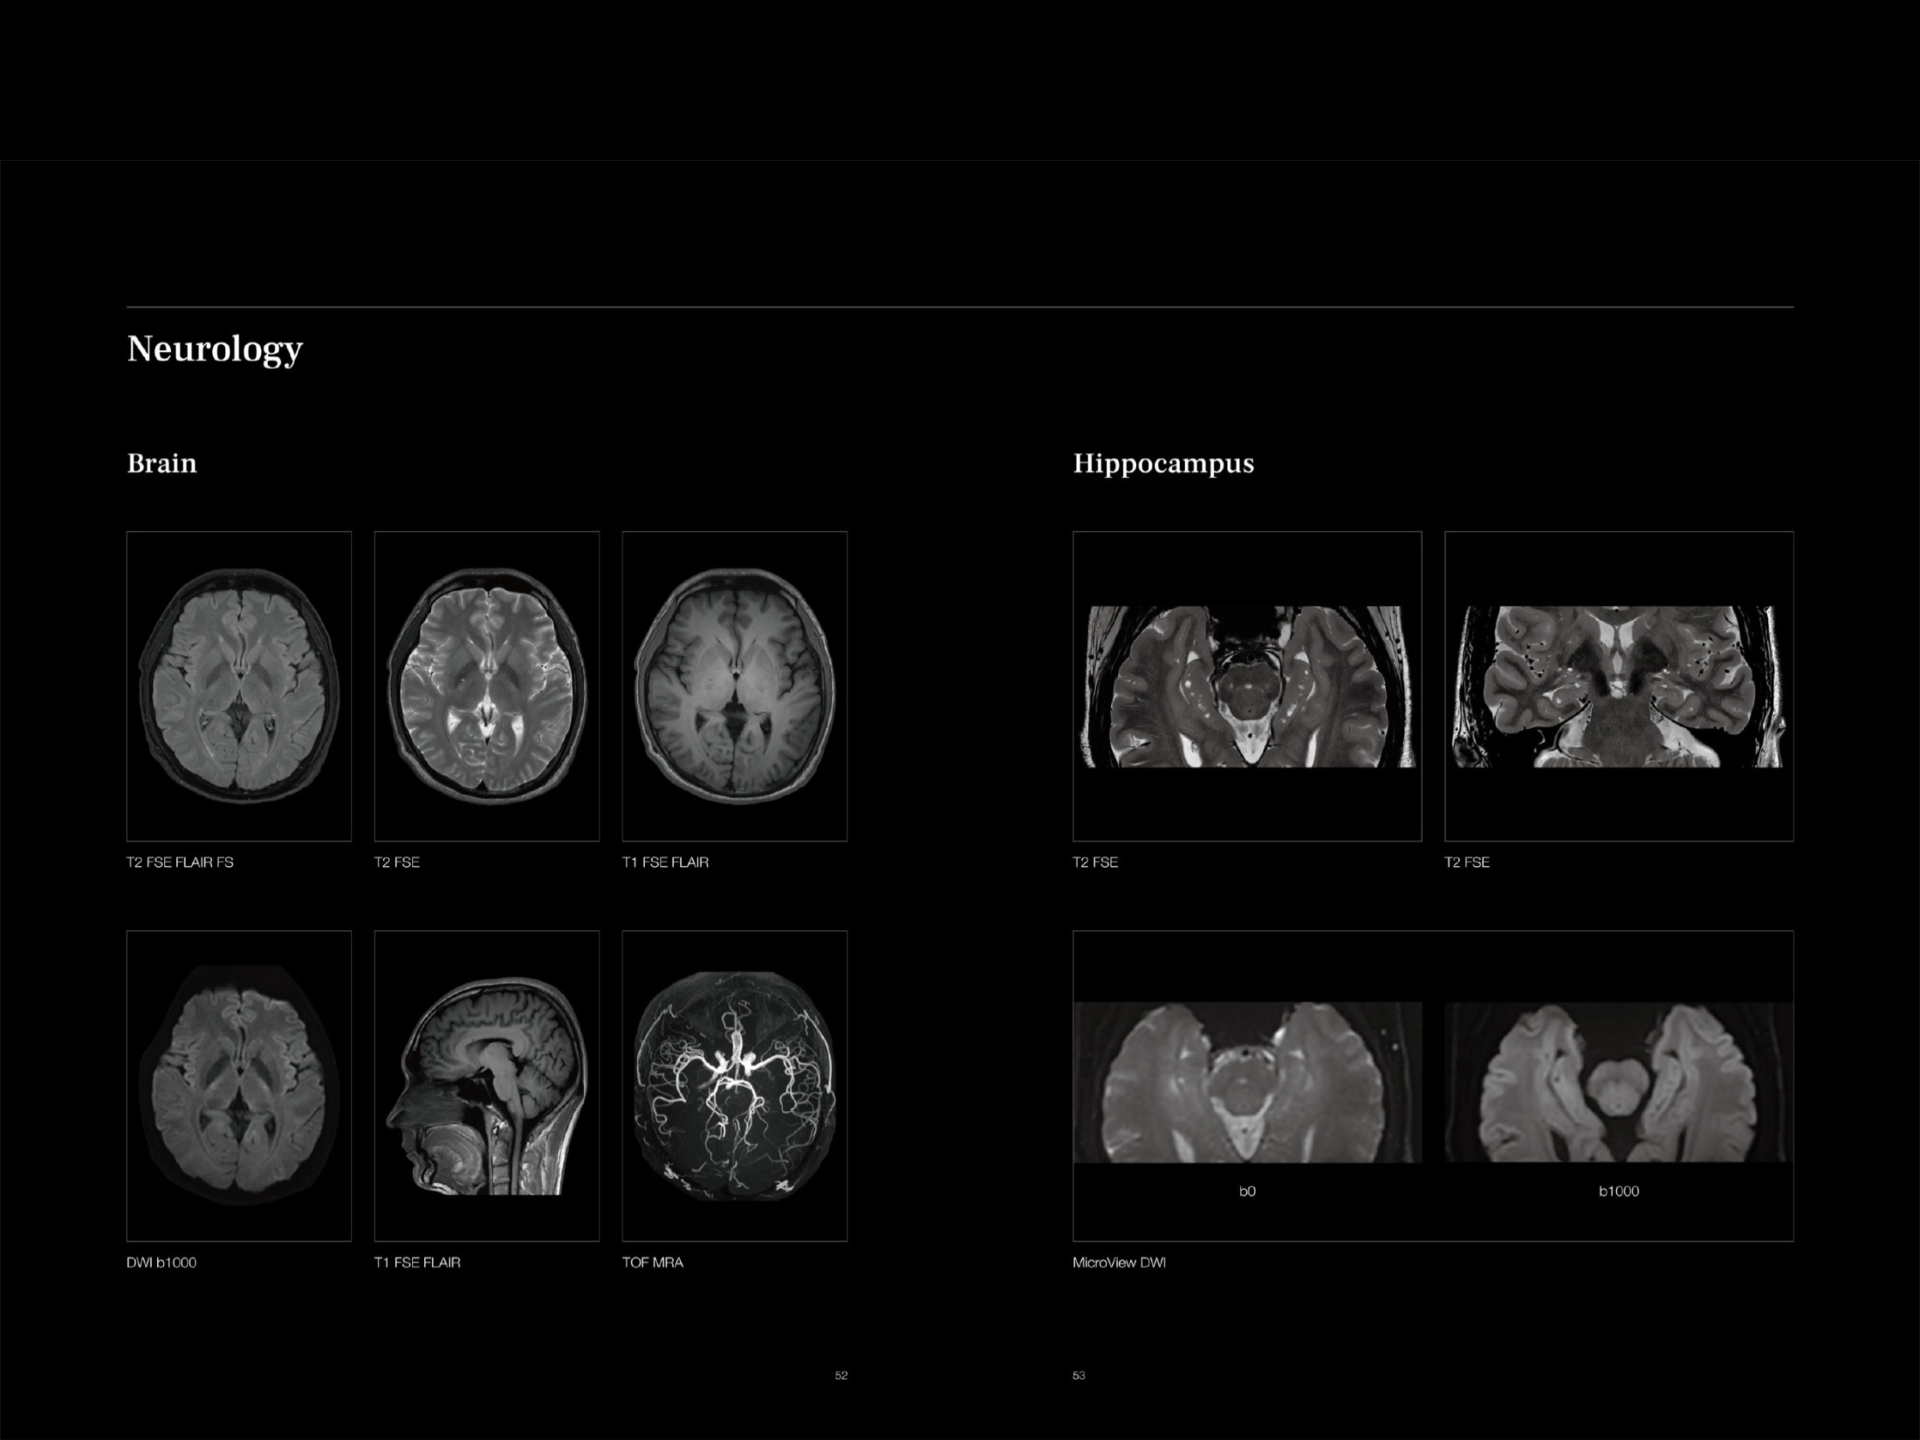

GIC Prime is equipped with the world’s highest strength 3T MRI with AI guidance and a wide bore of 75 cm.

Machine has 24 dedicated Superflex body coils designed for comfort and coverage for whole body MRI and special infant coil.